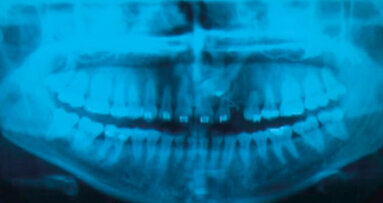

La presenza di malattie parodontali negletta o non adeguatamente trattata aumenta il pericolo di perimplantite e di perdita dell'impianto. I patogeni parodontali possono essere trasmessi dai denti naturali all'impianto, di conseguenza un regime estremamente meticoloso di igiene orale risulta un prerequisito indispensabile. Questo concetto, ben noto a tutti clinici, pur tuttavia non si fa mai abbastanza nel coinvolgere il paziente come principale terapeuta di se stesso: in altre parole in qualità di educatori svolgiamo la motivazione in maniera sufficiente e idonea?

La perimplantite è un processo infiammatorio che colpisce i tessuti che circondano un impianto dentale osteointegrato. È caratterizzata da infiammazione ...